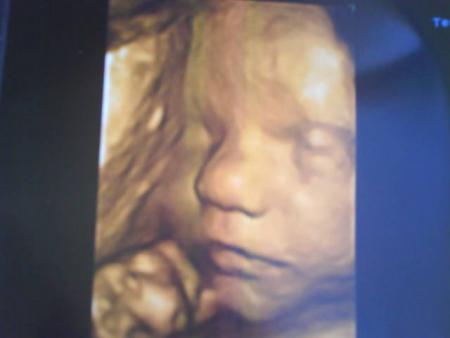

Bébé Yanis

27/07/2008 14:39 par bouille

Et voici la dernière en date, elle date du 8 Juillet 2008 donc bébé à 8 mois de conception...

Alors à qui il ressemble?